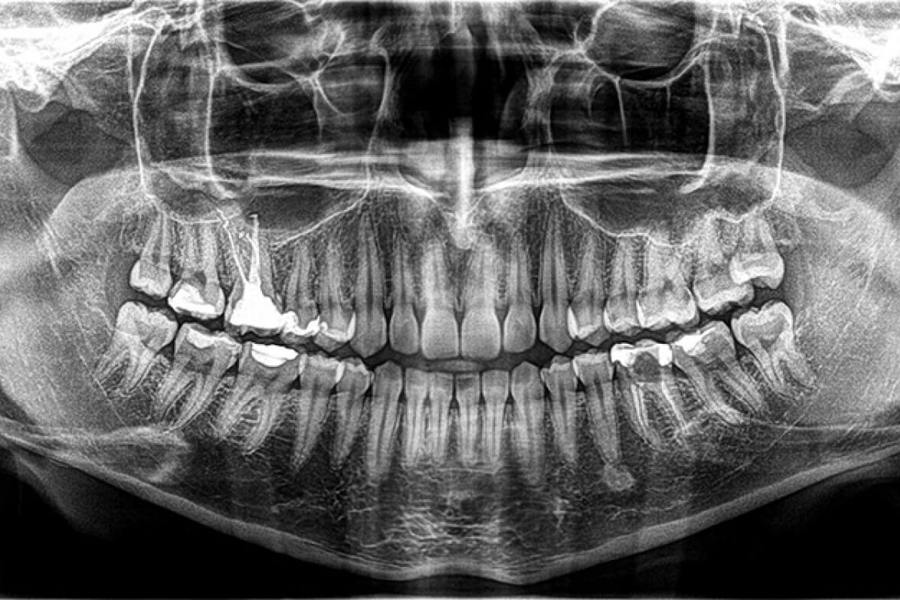

Zahvaljujući naprednoj CBCT (kompjuterska tomografija s konusnim zrakama) tehnologiji u samo 30 sekundi napravit ćemo trodimenzionalni snimak vaših zubnih struktura.

Prednosti CBCT snimka: